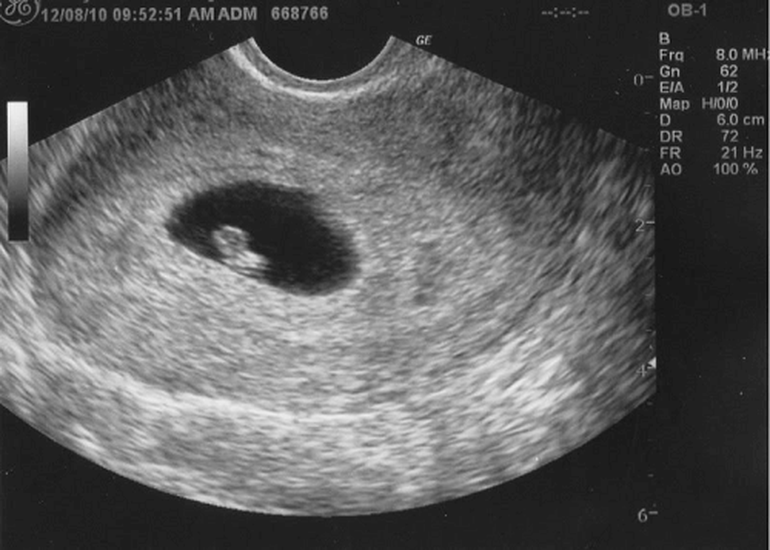

Siêu âm thai kỳ đầu (tuần 6-10)

Giai đoạn đầu của thai kỳ là thời điểm cực kỳ quan trọng để xác định sự sống của thai nhi cũng như tuổi thai. Việc tiến hành siêu âm trong khoảng thời gian này giúp mẹ bầu nắm bắt được những thông tin cần thiết để chăm sóc bản thân và thai nhi một cách hiệu quả.

Xác định vị trí thai

Việc xác định vị trí thai trong tử cung là điều hết sức cần thiết. Qua siêu âm, bác sĩ có thể đảm bảo rằng thai nhi đang phát triển đúng vị trí trong tử cung, loại trừ khả năng thai ngoài tử cung – một tình trạng nguy hiểm đến tính mạng của mẹ và bé. Điều này đặc biệt quan trọng bởi vì thai ngoài tử cung có thể gây ra nhiều biến chứng nghiêm trọng nếu không được phát hiện và xử lý kịp thời.

Xác định vị trí thai cũng chính là bước đầu tiên để bác sĩ đánh giá sự phát triển của thai nhi trong giai đoạn này. Nếu thai nhi nằm ở vị trí bình thường, mẹ bầu có thể yên tâm hơn trong quá trình mang thai tiếp theo.

Kiểm tra hoạt động tim thai

Một trong những yếu tố quan trọng nhất để đánh giá sức khỏe của thai nhi là hoạt động tim thai. Siêu âm ở tuần thứ 6-7 có khả năng phát hiện nhịp tim thai, bên cạnh đó còn giúp bác sĩ đánh giá nhịp tim có ổn định hay không.

Hoạt động tim thai bình thường là dấu hiệu cho thấy thai nhi đang phát triển khỏe mạnh. Nếu phát hiện bất thường, bác sĩ sẽ có kế hoạch can thiệp kịp thời để bảo vệ sức khỏe của bé.